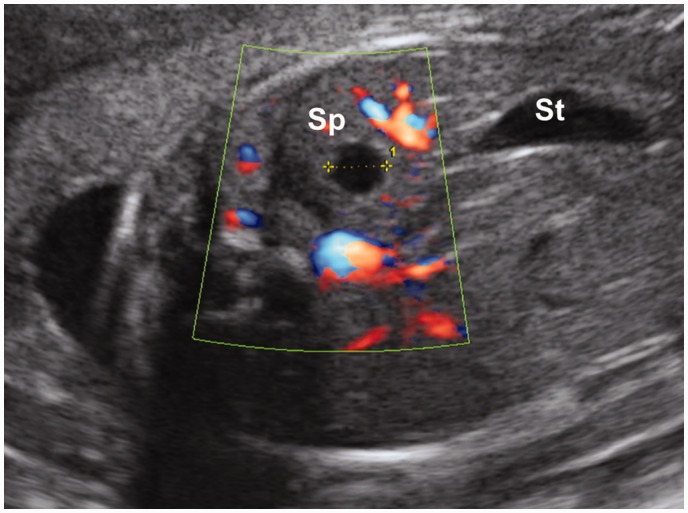

基因检测单位名称:江西省萍乡市基因检测应用中心。现有病例 32 例,共新增 9 例。 在脾脏囊肿基因检测的所有病例中,除了一个病例,脾囊肿的产前检测是在妊娠晚期进行的,诊断时的中位孕龄为 30 周(范围 22-37)。 除 1 例失访外,均在分娩后确诊为脾囊肿。 其余 8 例产后超声检查显示,2 例 (25%) 囊肿增大,1 例 (12%) 大小稳定,1 例 (12%) 囊肿缩小,1 例完全消退 四例(50%)。 婴儿中没有与囊肿相关的并发症的报道。其他成熟基因检测项目:疫苗特异性抗体反应降低肿瘤基因检测, 3-甲基戊二酸尿症基因体检

A closed sac located in the spleen.